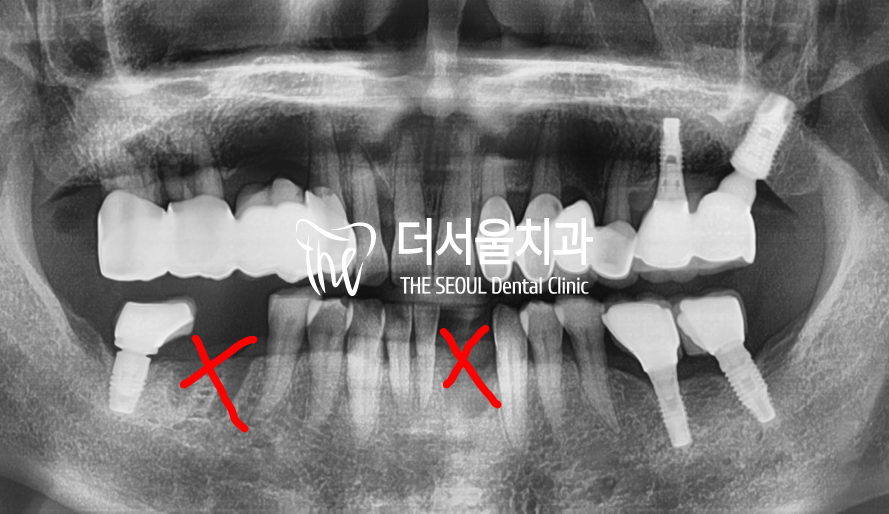

사진을 보면 2곳에 치아 발치가

이루어져 있죠?

제가 앞니쪽에만 설명을 드렸었는데

이 분의 경우 하악에 어금니에

인접면 우식증이 광범위하게

나타나 있었기 때문에 치료 불가였었습니다.

결국, 1개만 임플란트를 하려다

2개가 된 셈이죠.